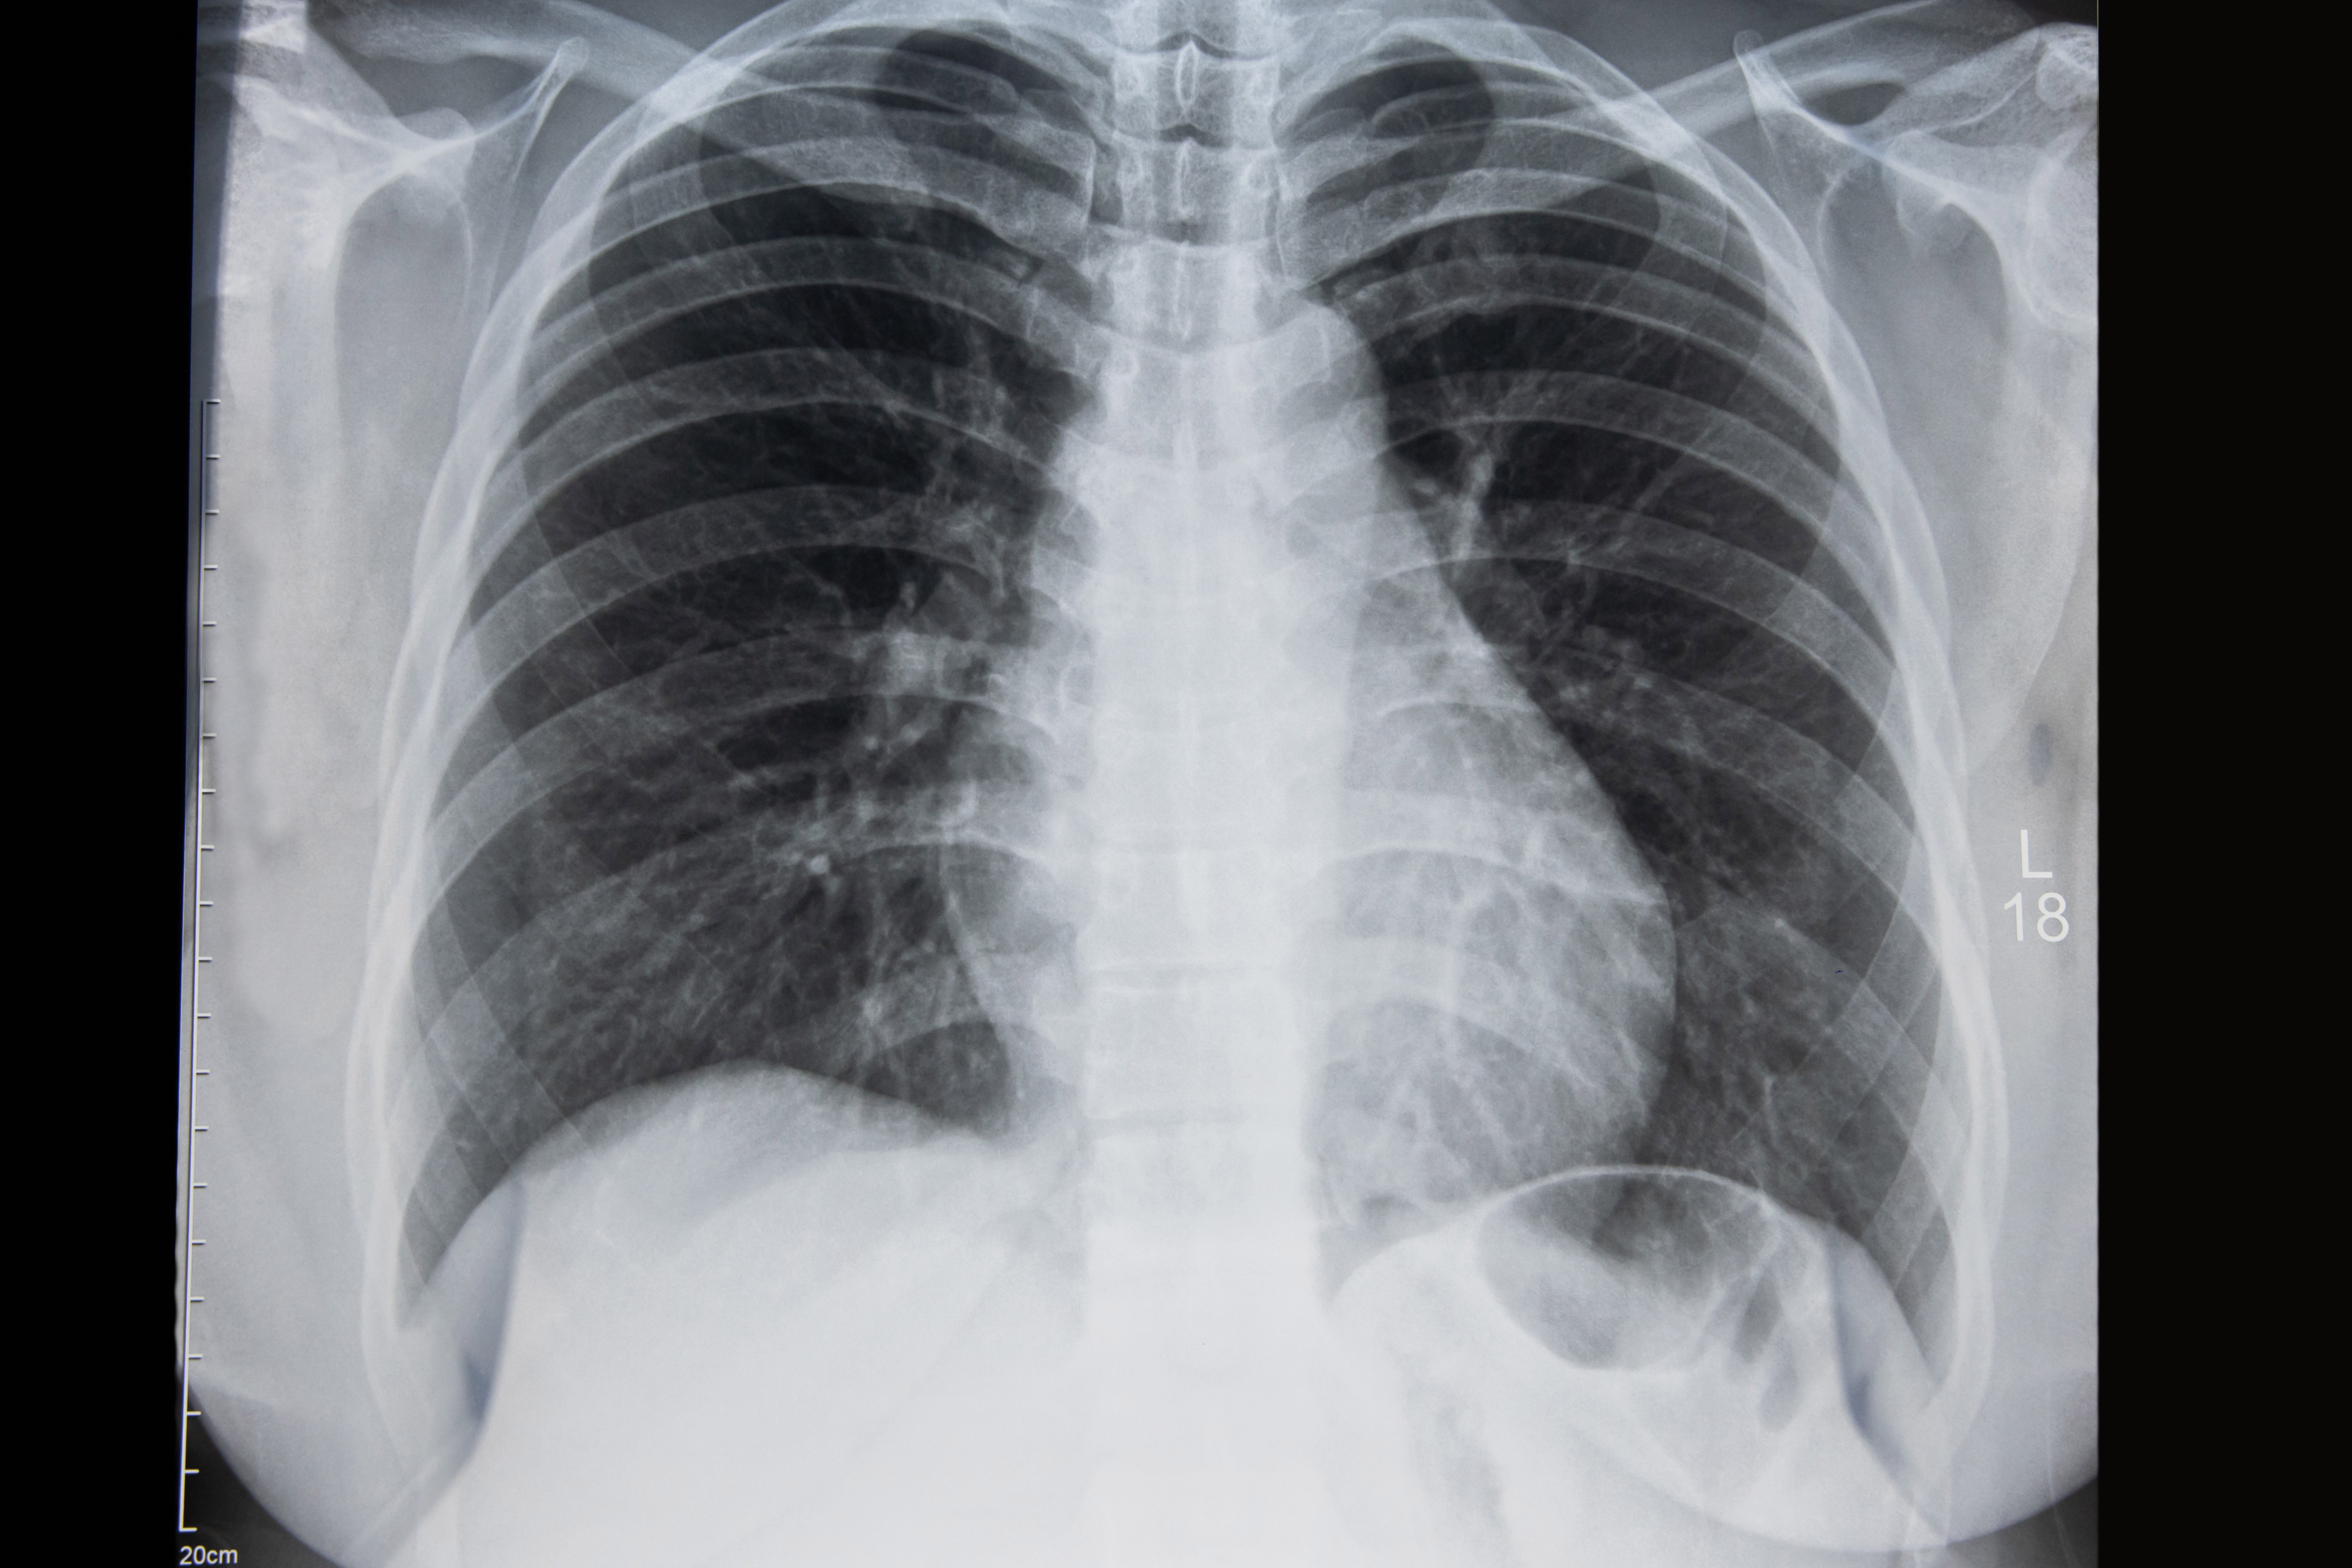

Screening means testing for a disease when there are no symptoms. Low-dose CT screening of the chest looks for lung nodules which may be early lung cancer. This offers the best chance of finding lung cancer in its earliest and most curable stages. During the screening, you will lie on a table that passes through the center of the scanner. The screening CT can be performed with a single short breath-hold and takes less than 15 seconds. The procedure is painless. The benefit of finding and treating early lung cancer far outweighs the risk.

The amount of radiation exposure from CT lung cancer screening is about the same as a person would receive from background radiation (such as sun exposure) over a period of one year. A radiologist will interpret your screening chest CT and either recommends a one-year follow-up or further testing. Results are sent to your physician. You will receive a follow-up call from the lung patient navigator and a letter with your results.